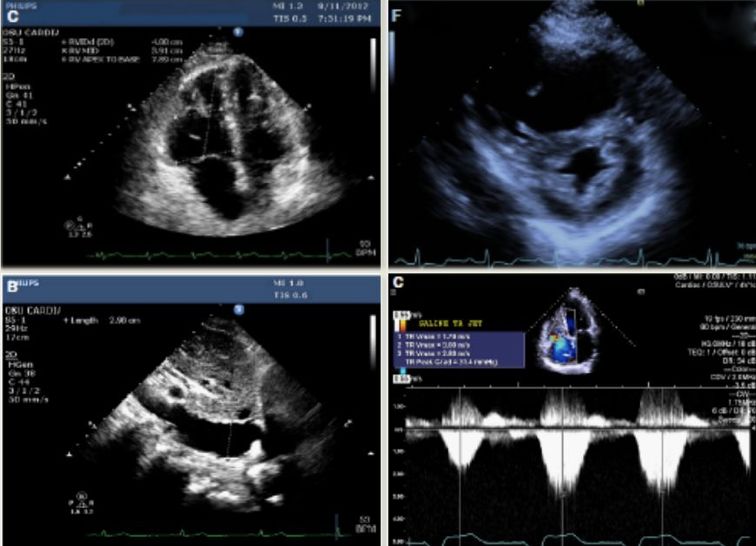

LA 6.30cm

LVD 3.00cm

RVD 2.60

RVSP 82mmHg

• 超声心动图

• 右心室结构:室壁厚度;腔室大小:内径、面积、容积;

-右室纵向收缩功能:TAPSE、脉冲组织多普勒S波、定量组织速度成像S波、GLS

• 右心室舒张功能